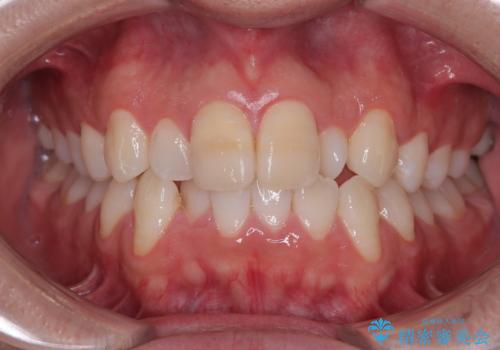

最新の症例

Latest cases